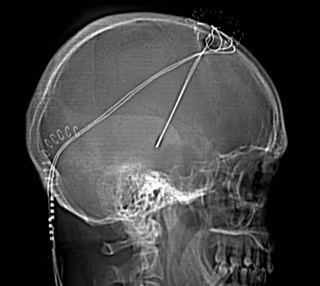

HOSPITAL BELLVITGE